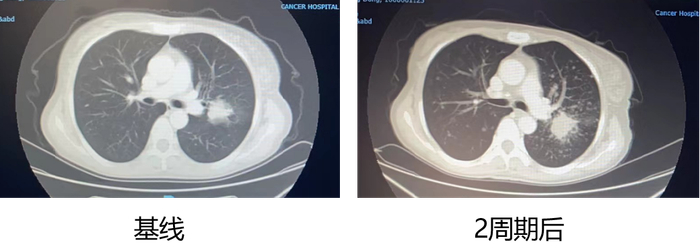

2022年5月13日至2023年2月8日,三线治疗应用奥希替尼(80mg qd po)+达拉非尼(150mg bid po)+曲美替尼(2mg qd po),最佳疗效SD。

2023年2月8日,患者复查胸部CT提示“肺部病灶增大”,考虑PD,三线PFS 9个月。